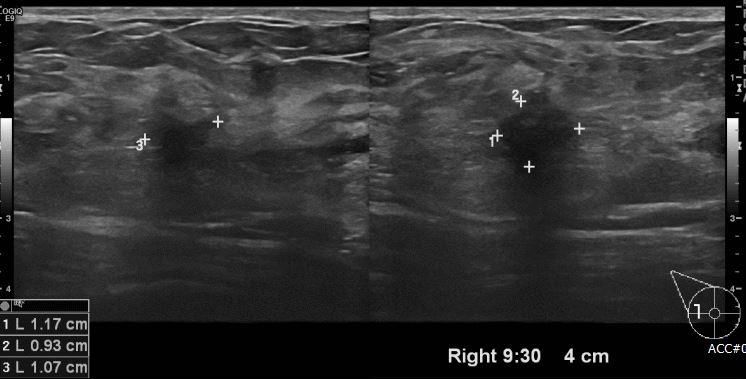

상기환자 건강검진상 이상소견으로 내원하신 50대 여성 분으로 우측 9시 30분 방향에서

4cm 떨어진 거리의 의심스러운 혹 조직검사 시행하여 우측 유관암 진단 되었습니다.